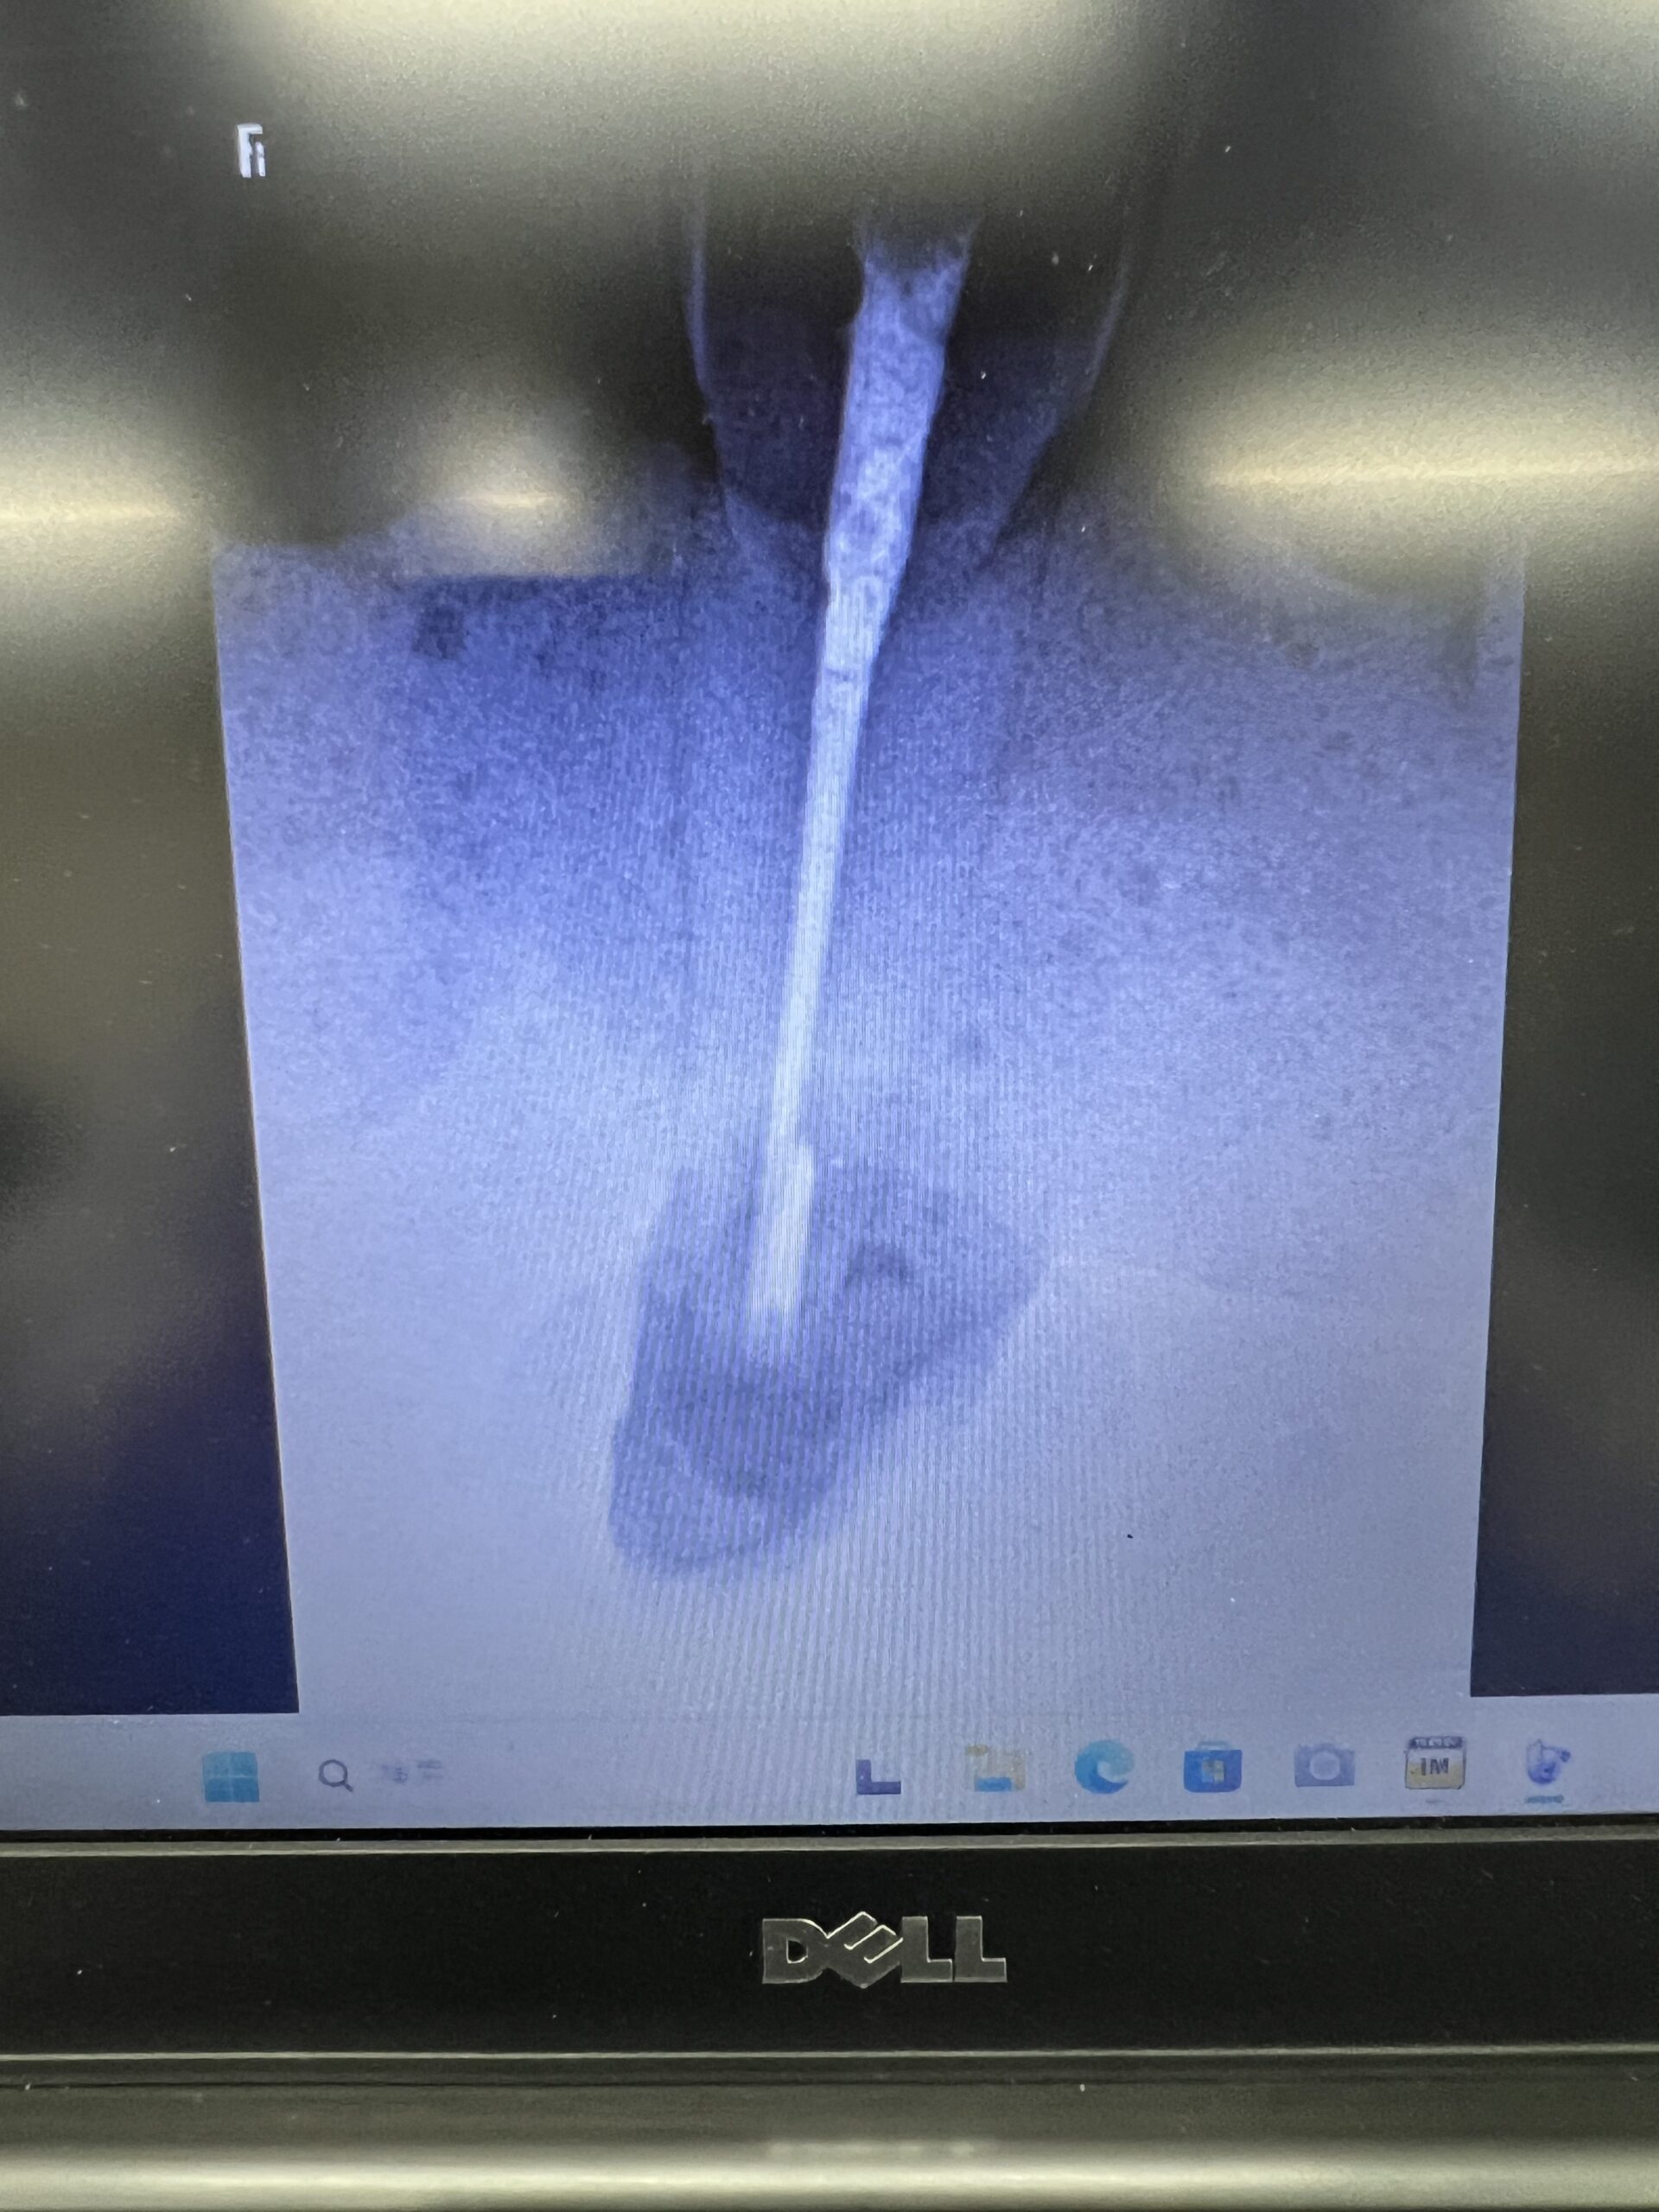

気泡が入り、しょっぱい逆根充になったのでこの受講者はやり直した。

以下だ。

気泡が入っても厳密にはやり直し不要だが、

“いいPAの絵”を得よう思えばやり直しが必須だ💢 それが専門医なのだから”

と、USC時代もDr.Schechterに指導されたことを思い出す。